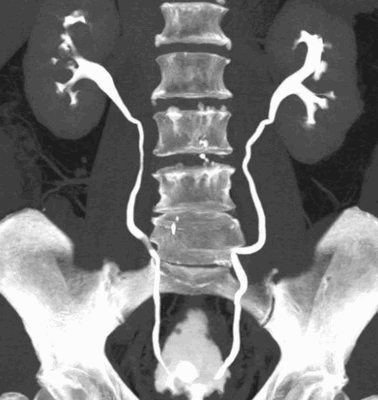

КТ органов мочевыводящей системы с усилением

проведении комплексного урологического исследования - КТ мочевыводящих путей показывает функцию каждой почки в отдельности, препятствие к оттоку урины на любом уровне, патологические рефлюксы, кисты и пр.